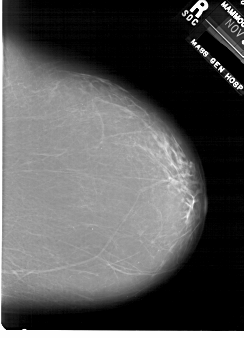

A_1876_1.RIGHT_MLO

RIGHT_MLO LINES 6871 PIXELS_PER_LINE 4861 BITS_PER_PIXEL 12 RESOLUTION 43.5 NON_OVERLAY